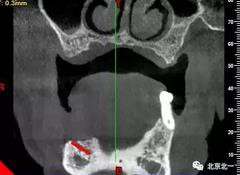

術(shù)前檢查片下頜骨季度萎縮,右側(cè)下頜下牙槽神經(jīng)管幾乎位于牙槽嵴頂。不能行常規(guī)種植。采用A04技術(shù)可實(shí)現(xiàn)即即刻種植一日戴牙夢想。

圖一至圖六明顯看出右側(cè)頦孔位于牙槽嵴頂。很清晰看出頦孔區(qū)的U型形狀。